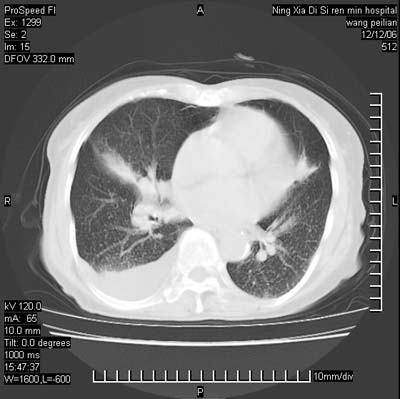

标题: CT5609:胸部:女77 病史不详

两肺可见多个大小不等的结节,左侧有胸水,纵隔淋巴结增大,考虑是细支气管肺泡癌

两肺尖纤维索状影,两下肺结节块状影,且有钙化灶,右胸腔积液。考虑肺结核并胸膜炎。

两肺尖纤维索状影,两下肺结节块状影,且有钙化灶,右胸腔积液。考虑肺结核并胸膜炎肺间质纤维化

考虑:1、慢性支气管炎合并全小叶型肺气肿、间质纤维化;

2、双肺结核;

3、右侧胸膜炎(积液)。

1、双肺继发型肺结核(以纤维、增殖灶为主);

2、右侧胸腔积液;

3、其余符合老年肺改变。

双肺见多个结节状及条索状影,双侧胸腔积液,右侧叶间积液,考虑结核性胸膜炎